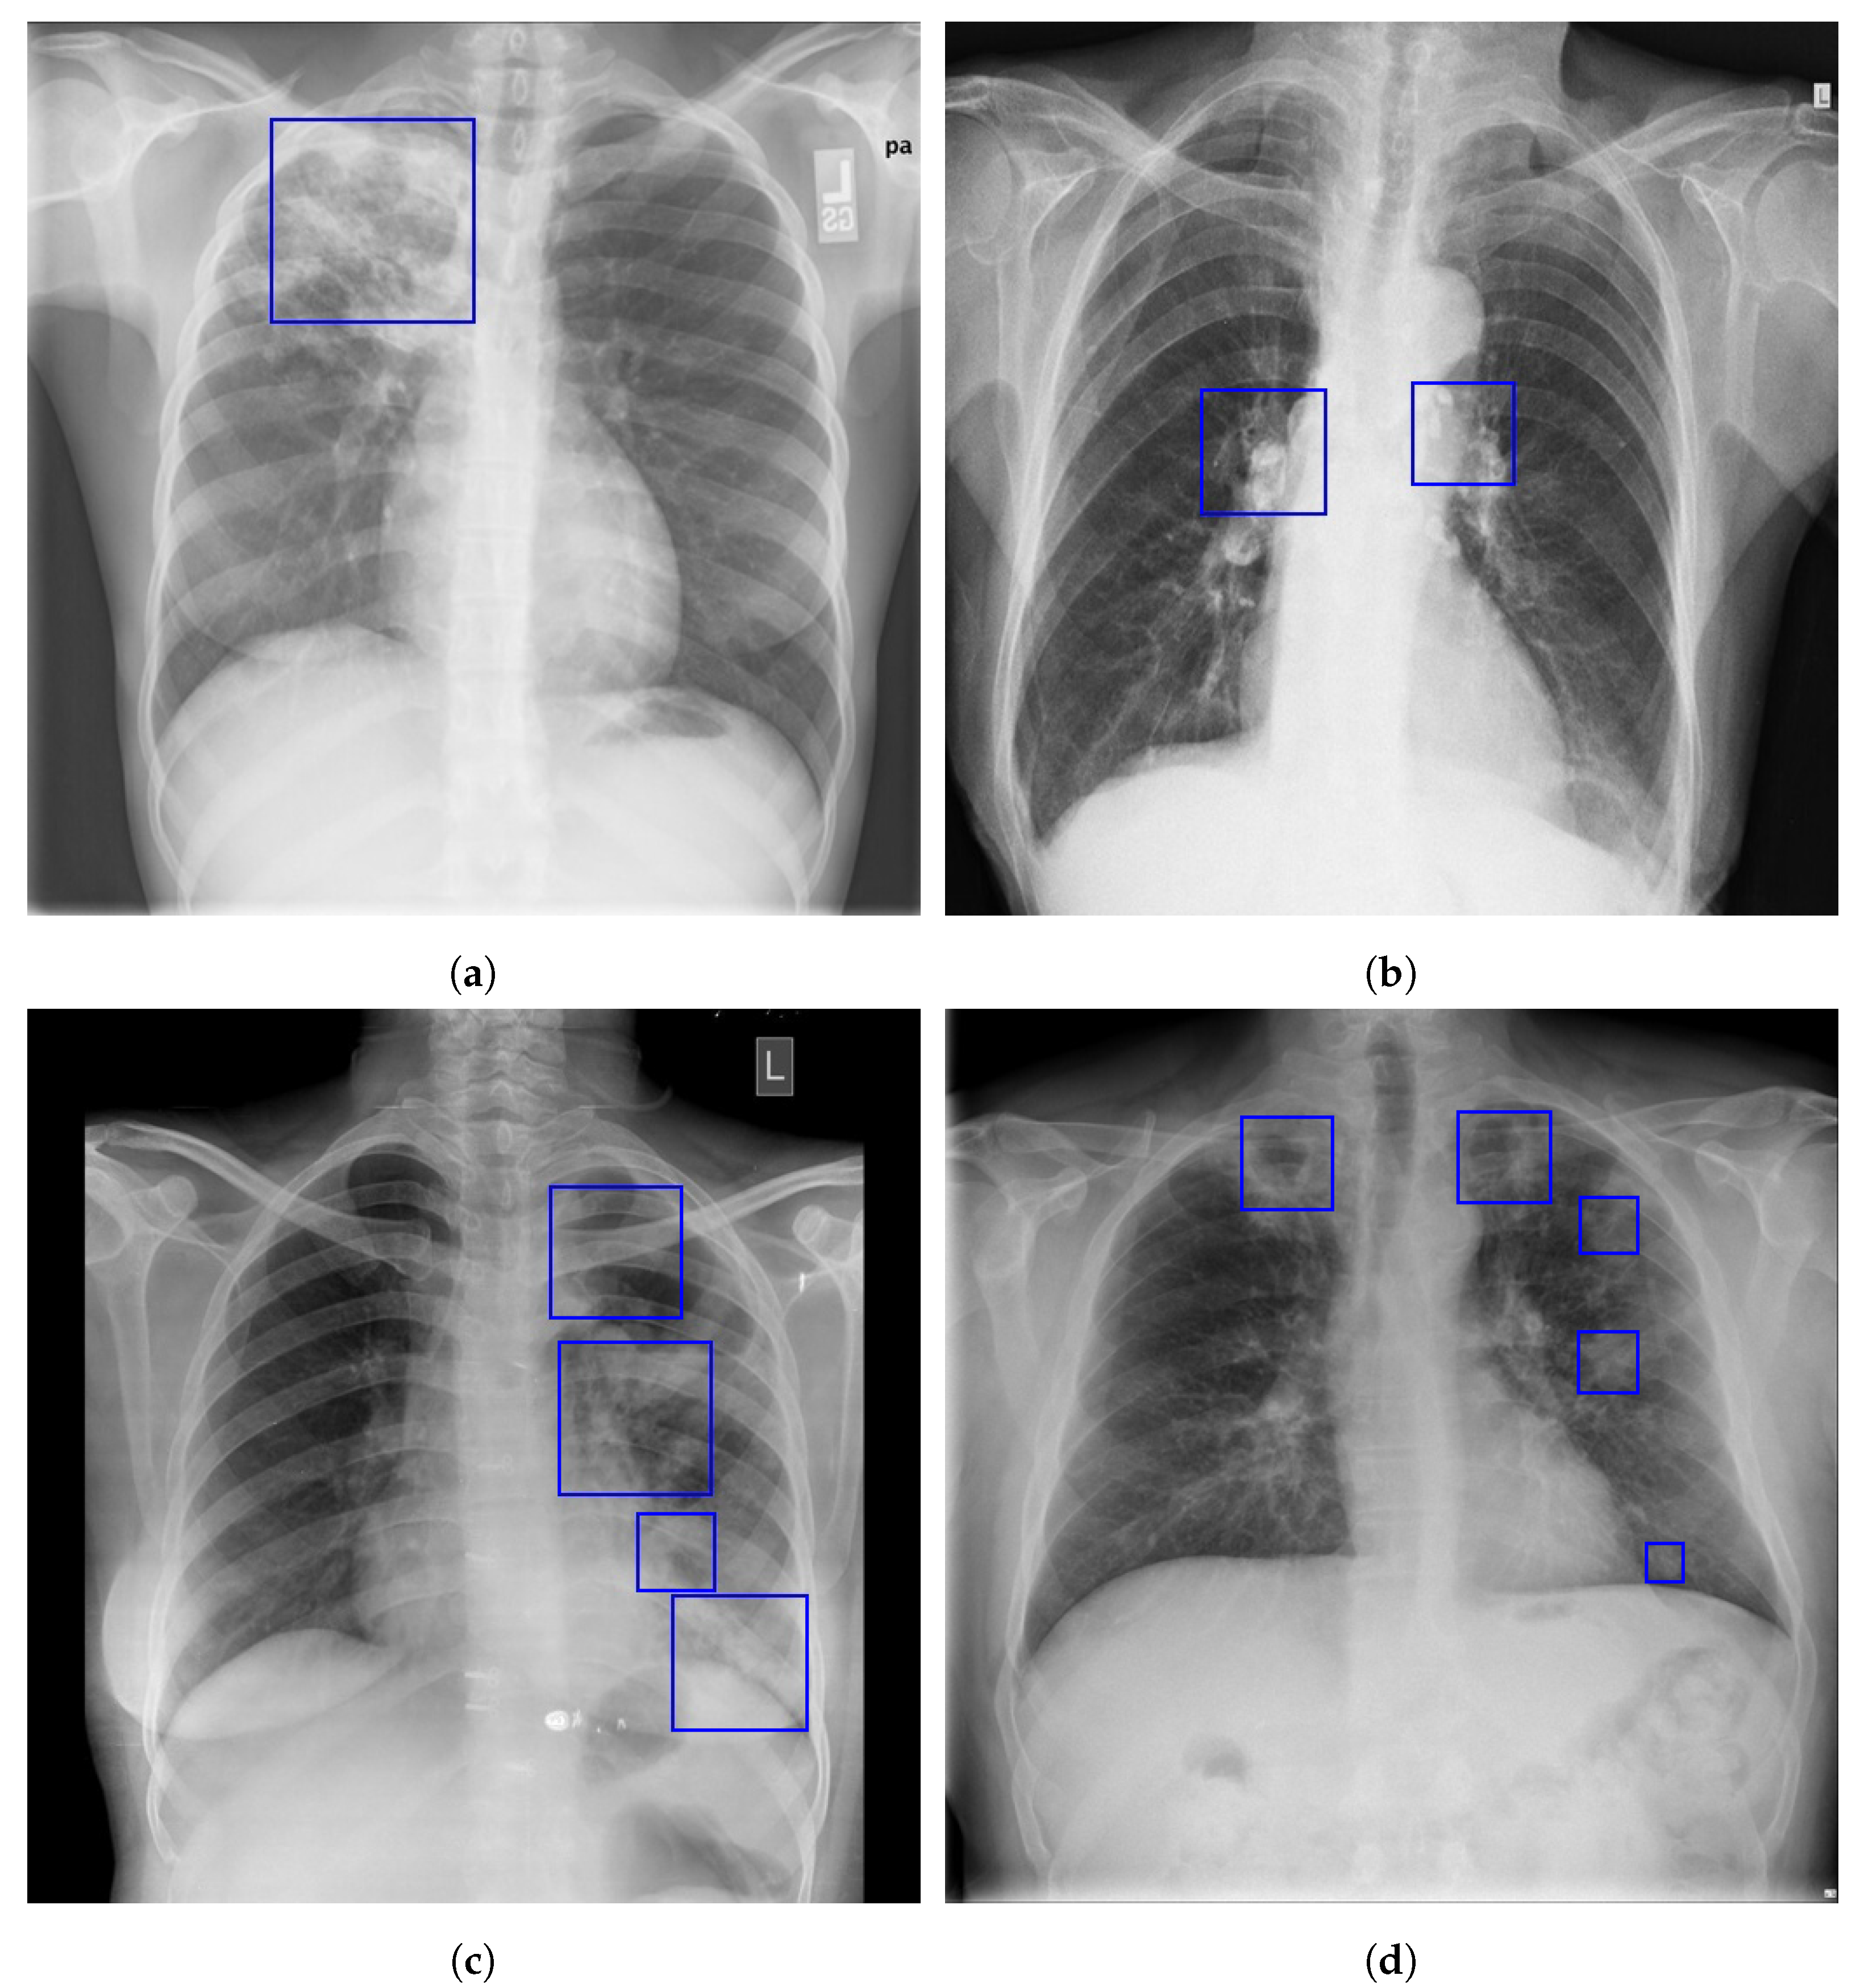

1.2. Radiographic Features of Pulmonary TB

1.3. Localization of Pulmonary Tuberculosis in a Chest X-ray